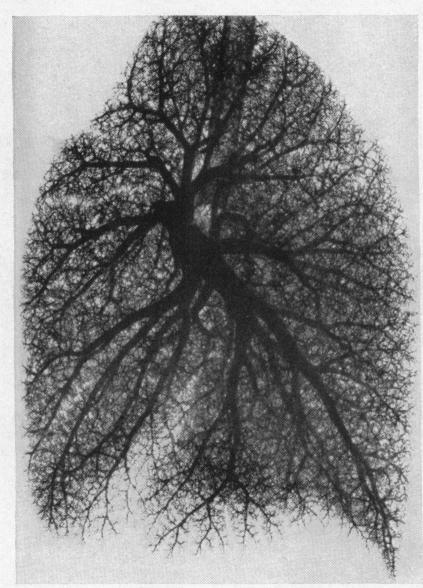

Solitary pulmonary hypertension.

Br Heart J. 1957 Jan;19(1):93-116. doi: 10.1136/hrt.19.1.93.